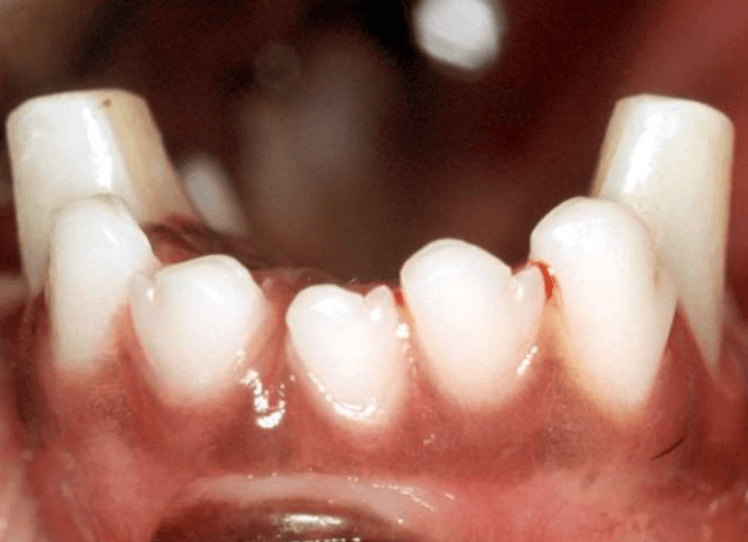

Let’s keep those canines around - this is a procedure used to preserve teeth when canines are mandibularly displaced.

What is crown reduction?